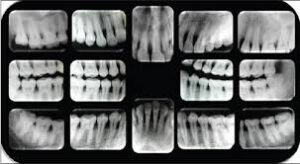

HOWMANY X-RAY IN A FULL MOUTH SET :-

An FMX seriese of 18-20 x-rays which includes all 4 bitewings and PA’s of every tooth.